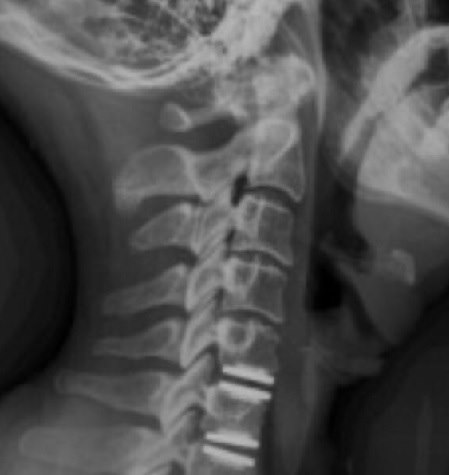

היצרות עמוד שדרה. צילום: ד"ר ליאור מרום

בשני המקרים, מדובר בהיצרות קריטית בקוטר תעלת עמוד השדרה הצווארי לקטרים נמוכים מ-10 מ"מ. ועקב כך, פגיעה בתפקוד הגפיים.

בין אם מדובר בתוצאה של לחץ דיסק ובין אם מדובר בשינויים ניווניים - אבחון מדויק של התסמינים הקליניים דורש הדמיית MRI של הצוואר, המאפשרת אבחנה סופית. בהדמיה נראה בבירור את הלחץ על חוט השדרה הצווארי ואת ההיצרות בקוטר התעלה. בחלק מהמקרים, נראה גם אות חריג המגיע מחוט השדרה הצווארי.